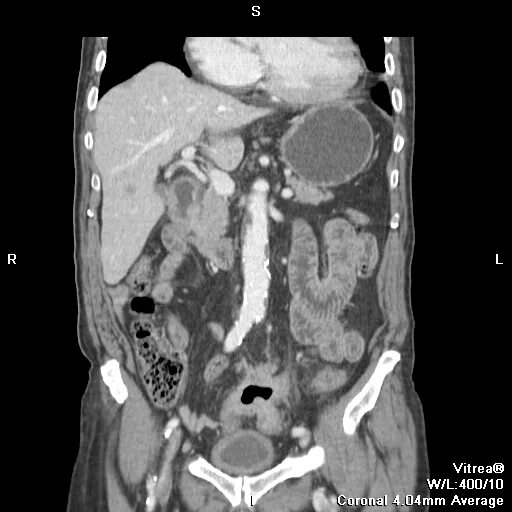

Метастазы в легких прогноз 4 стадия